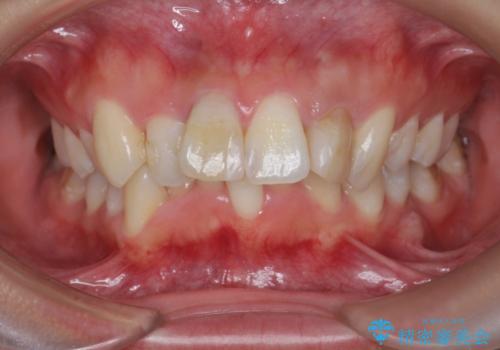

[ マウスピース矯正 ] 出っ歯に見える前歯を改善したい

- 「出っ歯に見える前歯を改善したい。」と矯正治療を希望され来院されました。

・2級性の咬合関係(上顎前突) ・前歯の傾斜

を改善すべく、マイクロインプラントを用いた奥歯の後方移動を行い上記の問題を解決していきます。

マイクロインプラントを用いてしっかりと後方移動を行ったことで、奥歯の咬合関係・前歯の傾斜をしっかりと改善し、機能的・審美的に大きく改善する矯正治療を行うことができました。